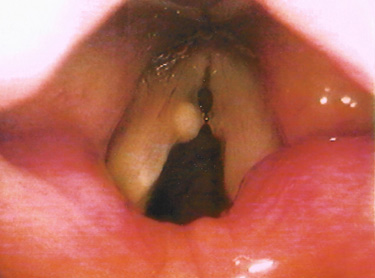

Epidermoid cyst is trivially protruded in the vocal cords while mucosal retention cysts usually develops under the vocal folds membrane then protruded inside the larynx.

It is important to discern vocal cyst from other laryngeal diseases like vocal nodules or polyp when diagnosing the problem.